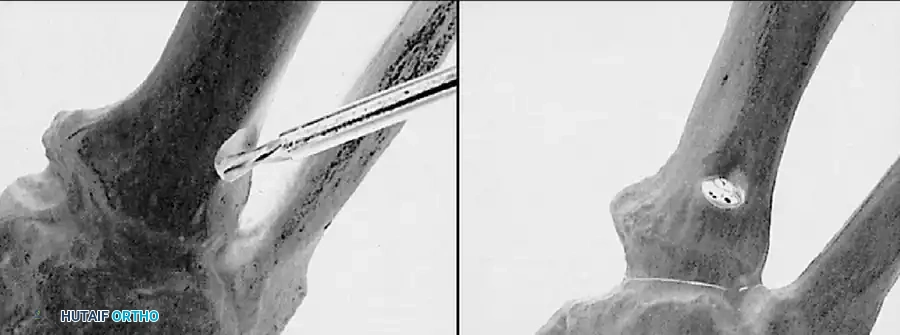

• Grasp the hallux in one hand and displace the proximal remnant medially so that, under direct vision, two longitudinal 0.062-inch Kirschner wires can be inserted.

• Hold the interphalangeal joint straight while drilling the wires from proximal to distal, emerging a few millimeters plantar to the nail plate.

• Return the foot to the corrected position, and drill the wires into the metatarsal head.

• While holding the metatarsal as far laterally as possible, cross the joint, and drive the wires out the plantar cortex just proximal to the head, while holding the hallux in 10 to 15 degrees of extension, neutral abduction, adduction, and rotation, and no translation dorsally or plantarward on the metatarsal head. The wires should penetrate only 2 to 3 mm past the cortex to avoid tenderness over the wires with weight bearing.

• If the Kirschner wires tend to “walk” on the rounded articular surface of the metatarsal head, use a small hemostat snugged up against the wire while it is being drilled to allow accurate placement. Proper placement of the wires and the desired position of the hallux on the metatarsal may require several attempts. The medial aspect of the proximal phalanx should not rest medial to the medial aspect of the metatarsal head.

• Place the hallux in the neutral medial-lateral plane and in 10 degrees of extension.

• Before the second wire is driven into the fi rst metatarsal head, place the hallux in proper rotation, using the plane of the nail as a guide. The initial length of the hallux is maintained by the wires. Later, collapse occurs when the wires are removed, but improved encapsulation of the hemiarthroplasty, by maintaining length for the fi rst few weeks, may help maintain a more desirable position long-term.

• Cut the wires off 2 to 3 mm distal to the skin edge.

• When the sesamoid has been removed, insert two 0.062-inch Kirschner wires retrograde from the tip of the toe 2 to 3 mm plantar to the nail bed, leaving about 5 to 7 mm of the pins exposed at the base of the phalangeal remnant to help align the phalanx on the metatarsal before antegrade passage of the pins into the metatarsal (Fig. 78-31F).

• While holding the fi rst ray straight with the foot vertical, have an assistant insert the wires from distal to proximal (Fig. 78-31G). Often these wires, which run through the fi rst metatarsal and hallux, hold the fi rst ray straight, and most of this correction is maintained after the wires have been removed.